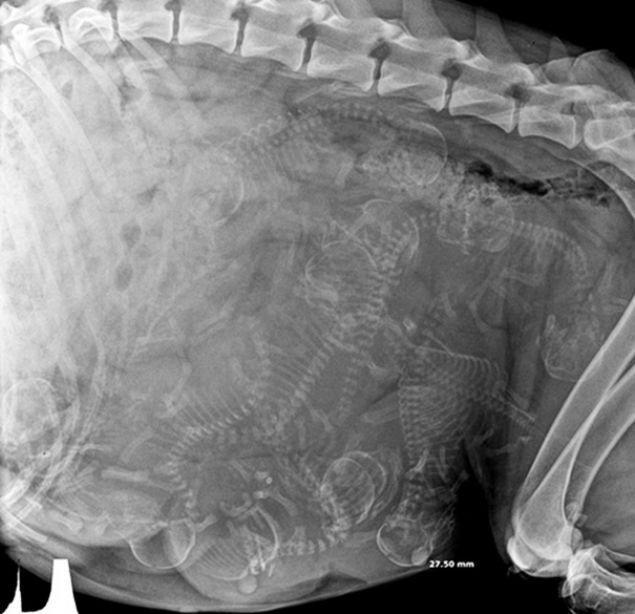

Hayvanların x-ray ile çekilmiş görüntüleri hayretler içinde bıraktı. Anne köpeğin karnındaki yavruları... Karınlarında yavrularını taşıyan hayvanların görüntüleri ortaya çok ilginç manzaralar koydu. Fotoğraftaki hamile bir maymun

Hayvanların hamilelik görüntüleri yılana bakın! - Resim: 2

Kaplumbağa